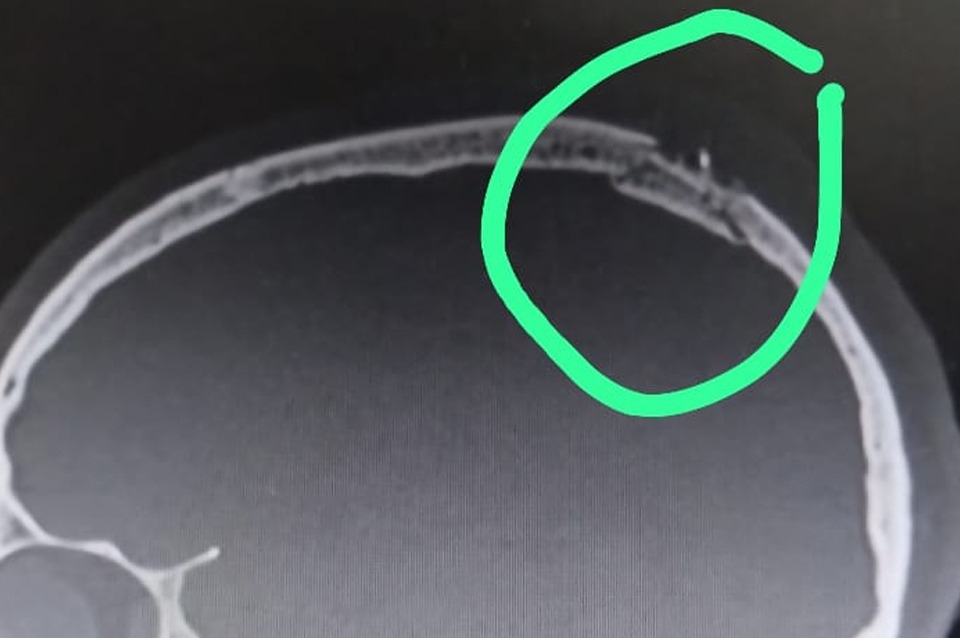

Le hacen una tomografía en la que no se percibe aparentemente  la fractura, por lo que los médicos le dieron el alta y le aseguraron que no tenía ninguna lesión.

En tanto, por la ART debe repetir la tomografía en donde se ve claramente la fractura de cráneo. "Tiene partida la cabeza y el médico que lo atendió en el informe puso que no hay lesión ósea", agregó indignada la madre.